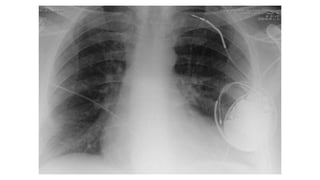

A 61-year-old man presented with worsening right thoracic pain and dyspnea three days after being discharged from cardiology following pacemaker implantation for sick sinus syndrome. A 60-year-old woman with an implanted pacemaker presented with dizziness and fainting. A 77-year-old woman who had a pacemaker implanted for symptomatic sinus bradycardia presented one week later with continuous chest pain. An elderly patient presented 6 months after pacemaker implantation with a recurrence of exertional shortness of breath.